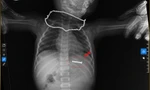

| Bé được tiến hành đặt ống xông dạ dày và rửa dạ dày bằng nước muối sinh lý trong khoảng 15 phút, cho đến khi dịch dạ dày trở nên trong. Qua phân tích, dịch dạ dày có chứa thức ăn, một ít thóc và một số dấu hiệu của thuốc chuột. Ảnh bệnh viện cung cấp |